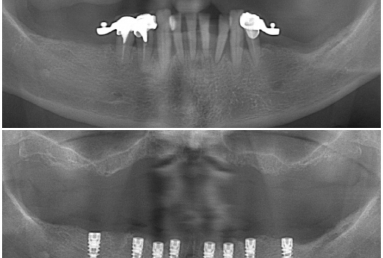

Our patient suffered from advanced periodontitis and we had to extract all mandibular teeth. After 2 month we inserted 8 Alpha Bio implants that healed in 4 months. All this time a full mobile temporary prosthesis was made, that was replaced in the end with fixed restorations made of porcelain fused to metal.

In the next step, tha patient wants to replace also the maxilary old mobile prosthesis with a fixed restoration.